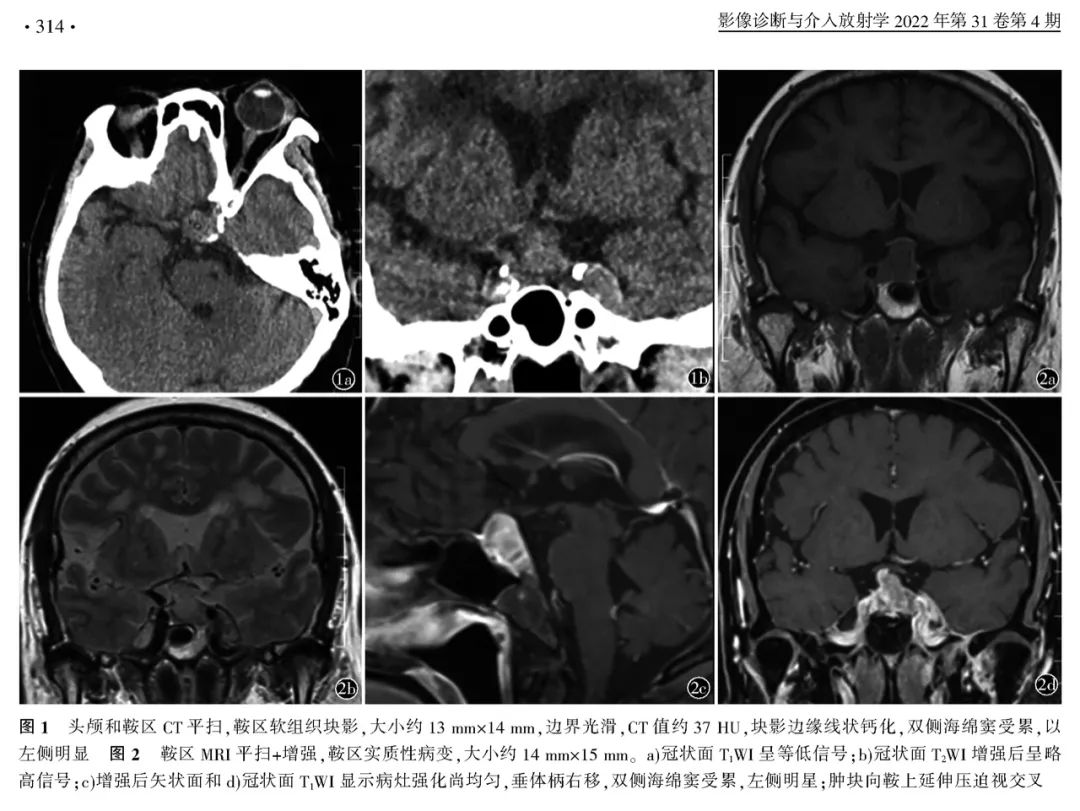

【病例】鞍区恶性肿瘤—非典型畸胎样/横纹肌样肿瘤1例CT及MR影像诊断思维-1

【病例】鞍区恶性肿瘤—非典型畸胎样/横纹肌样肿瘤1例CT及MR影像诊断思维-2